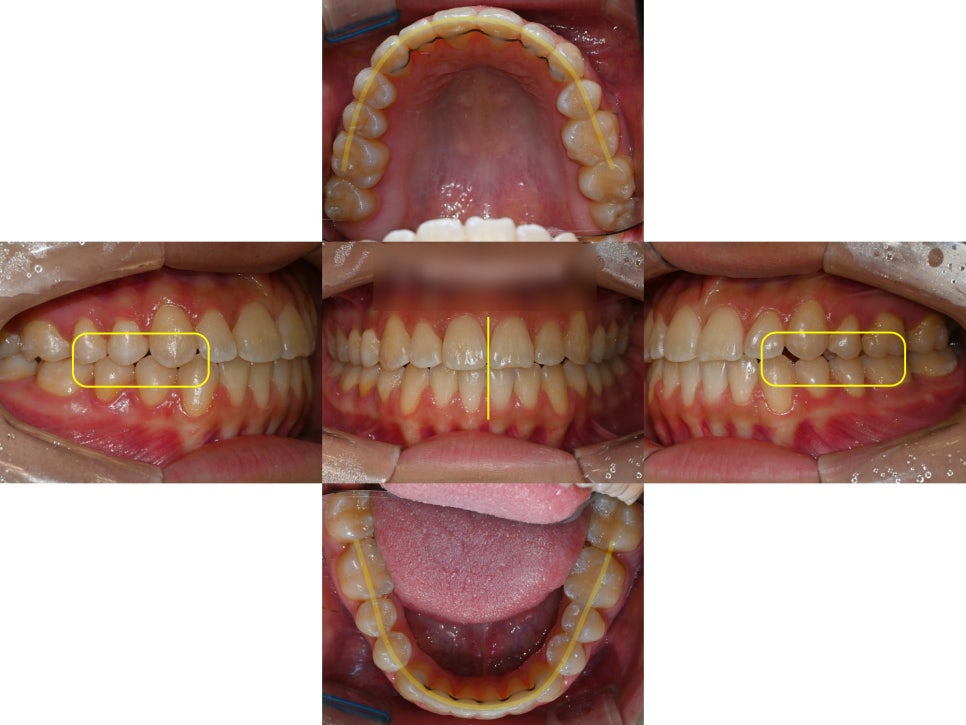

점점 긴밀해져가는

교합의 변화를 확인할 수 있습니다.

위아래턱의 폭경 부조화를 빠르게 캐치하고

급속구개확장장치(RPE)를 잘 활용한 덕분에

교합을 안정적으로 변화시켜줄 수 있었고,

심하게 틀어져 있던 정중선까지

최대한 맞춰드렸습니다.

가장 중요한 양쪽 어금니 교합이

잘 물리는 상태로 양호하게

마무리 된 모습입니다.